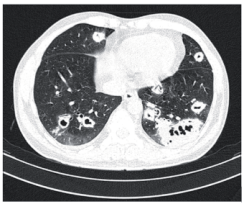

Mulher de 45 anos iniciou quadro de hemoptise e emagrecimento há 1 mês. Trouxe TC de tórax, sendo sua imagem mostrada abaixo. Pesquisa realizada de BAAR em 3 escarros espontâneos foi negativa. A TC de seios da face revelou sinusite. O EAS apresentava hematúria e proteinúria de 3+, confirmada em urina de 24 horas (1g de proteinúria). O hemograma era alterado apenas com anemia normocítica e normocrômica; a creatinina sérica era de 2,0 mg/dL, e a biópsia renal revelou glomerulonefrite pauci-imune. A biópsia de seios da face constatou presença de granuloma com necrose.

enunciado 578969-1 O diagnóstico dessa doença e o anticorpo que pode estar presente são, respectivamente,